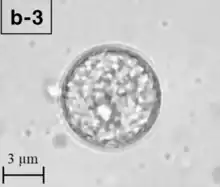

B. mandrillaris is a free-living, heterotrophic amoeba, consisting of a standard complement of organelles surrounded by a three-layered cell wall (thought to be made of cellulose), and with an abnormally large cell nucleus. On average, a Balamuthia trophozoite is about 30 to 120 μm in diameter. The cysts fall around this range, as well.[8]

Balamuthia's lifecycle, like the Acanthamoeba, consists of a cystic stage and a non-flagellated trophozoite stage, both of which are infectious, and both of which can be identified in the brain tissue on microscopic examination of brain biopsies performed on infected individuals. The trophozoite is pleomorphic and uninucleated, but binucleated forms are occasionally seen. Cysts are also uninucleated, possessing three walls: an outer thin irregular ectocyst, an inner thick endocyst, and a middle amorphous fibrillar mesocyst.[9]